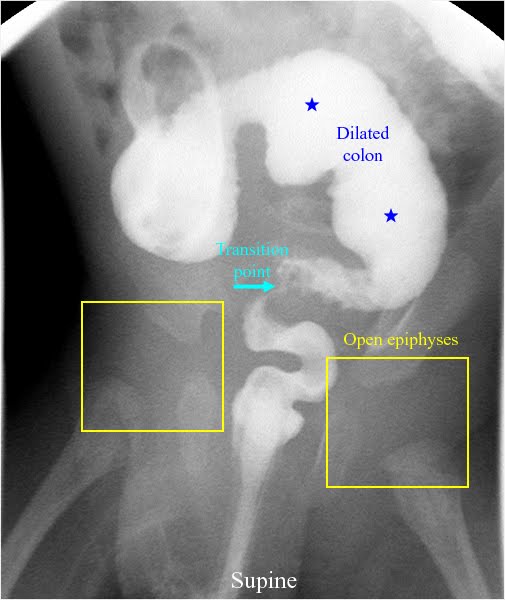

fonte: radiologyspirit.blogspot.com

Quando temos suspeita de de Doença de Hirschsprung (megacólon congénito) fazemos um Rx abdominal com ou sem contraste, que nos dá imagens muito típicas. Ainda assim, o diagnóstico definitivo é feito por biópsia rectal, onde se confirmam as tais alterações nervosas que descrevi acima. Dr. Dan lembra-se do megacólon, mas como a hipótese de se tratar de Doença de Hirschsprung foi aventada apenas muitos anos mais tarde, nunca se realizou a análise histológica (biópsia) da peça que confirmaria/ou negaria este diagnóstico. Ficará para sempre a dúvida.